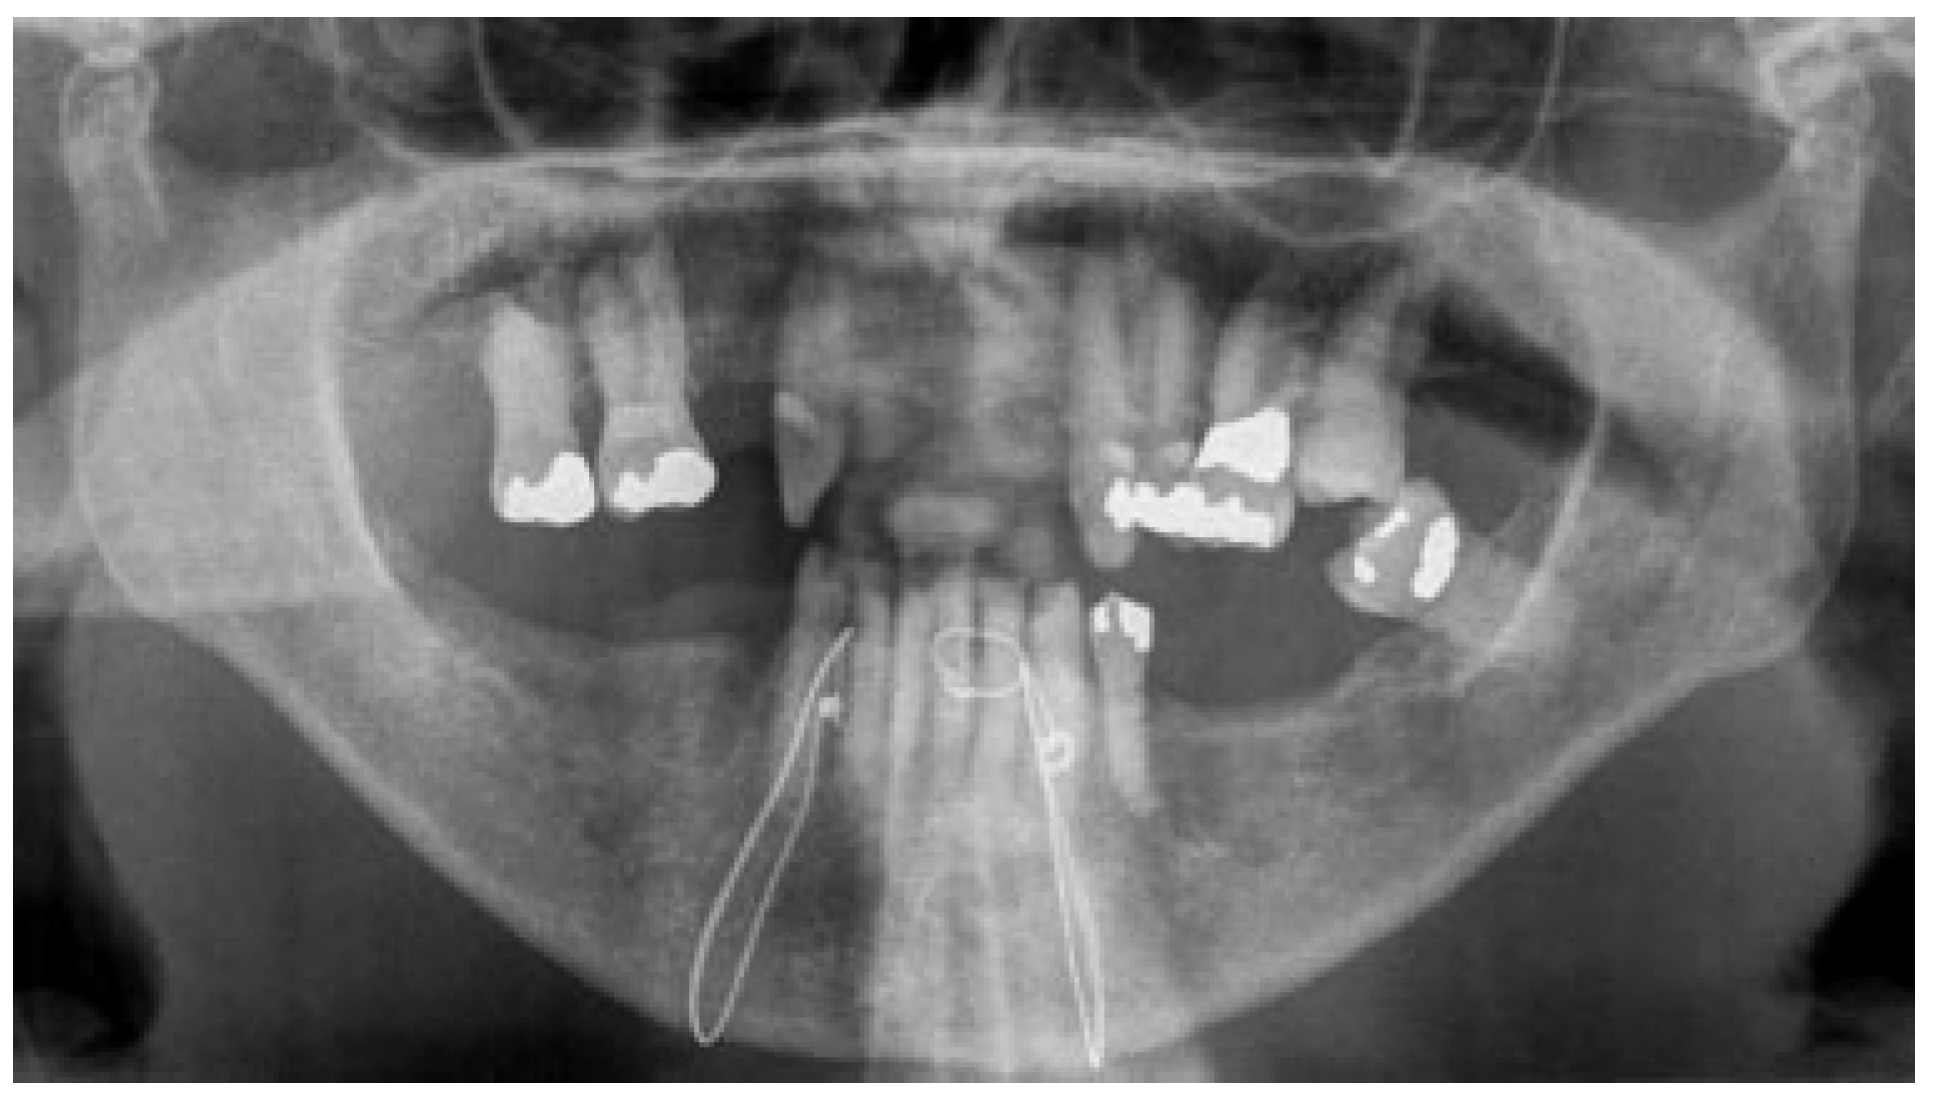

2.1. Case 1

2.2. Case 2